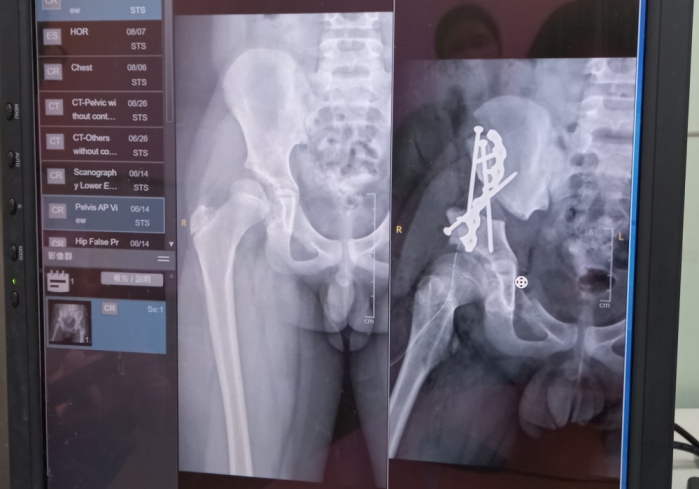

嘉基骨科姚樹鑫醫師表示,患者因幼兒時未能發現髖關節發育不良,成年後在劇烈活動時會感到疼痛,經休息情況會有所改善;但疼痛嚴重時,需服用幾天止痛藥才會緩解,當止痛藥效逐漸減弱,疼痛已嚴重影響走路,再加上病患本身以為只有人工髖關節置換手術,擔心術後會對運動造成限制,遲遲未對症治療,於是建議她進行髖關節保存手術。

姚樹鑫醫師說,「髖關節保存手術」是治療髖關節發育不良新的選項,可減緩疾病進展,保留自身的髖關節功能,特別是對於有運動需求,如瑜伽、舞蹈等需大角度活動的人來說,保留自身的運動能力和關節活動度顯得更加重要。嘉基骨科目前致力於推廣髖關節保存手術,術前,團隊會運用3D重組模型來模擬做出術前規劃,事先設計好最佳的轉動角度,並在複合式手術室中重組病患的髖關節影像,確保手術的準確性達到最高水平,以及能夠最大限度地保證病患的安全與縮短復原時間,並保留自然的髖關節功能才更為可貴。